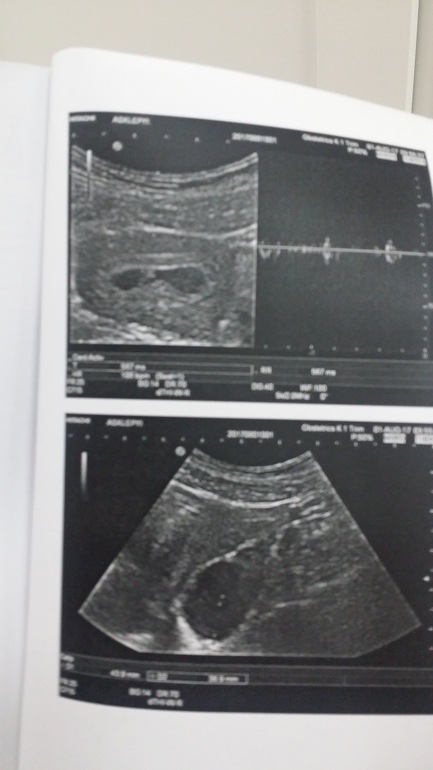

Ровно в 6 недель делали УЗИ. эмбриончик 3.5мм, сердцебиение 106уд/мин

У нас на 5+6 увидели сердечко

Мне в 6 нед и 1 день сердце показали. Количество ударов не замеряли, но на самом УЗИ было видно, как сокращается мышца. Так что все увидят уже при таком-то ХГЧ ;)

В период с 5 до 8 недель появляется СБ в любой момент , но обычно в 6 недель уже есть